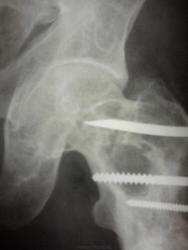

Двухсторонние литические очаги, с четкими, местами склерозироваными контурами. Старый консолидированый перелом левой бедренной кости, после металлоостеосинтеза металлической пластиной. Миеломная или мтс проявили бы себя более агрессивной деструкцией.

tatyana, Вам "зачет"! Здесь действительнро болезнь Реклингхаузена. Наблюдаю данного пациента лет 7. За это время его патологический перелом левой бедренной кости так и не срастается, приобретая все более атрофичный вид в виде перетяжки на уровне излома, потому и держат с металлом до сих пор. Классическая "пастушья палка". Справа в теле подвздошной кости и (менее выраженно) ближе к задней нижней ости, а также в большом вертеле также имеются литические очаги, относительно стабильные за время наблюдения.

"самоуверенность дилетантов - предмет зависти профессионалов"